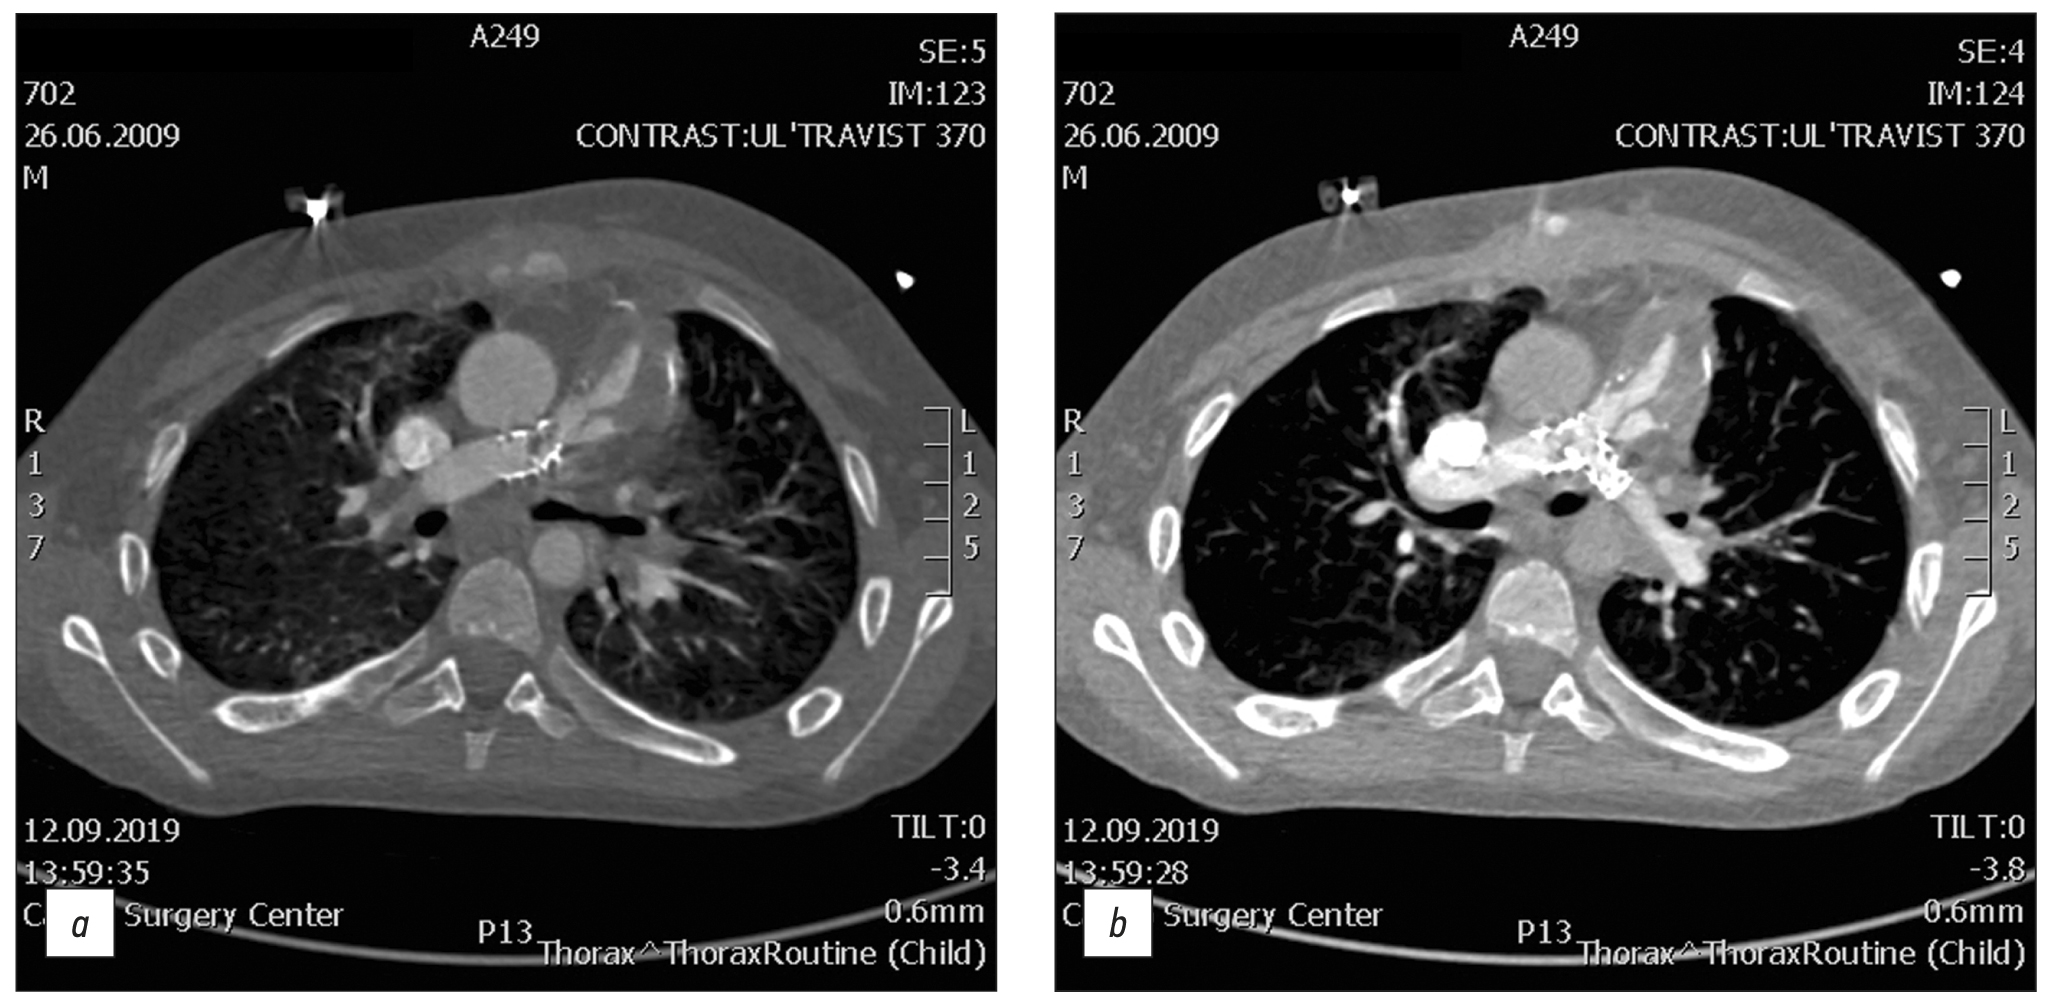

Результаты. Среди 116 пациентов с осложнениями после коррекции тетрады Фалло у 49 был стеноз лёгочной артерии, у 92 ― стеноз ветвей лёгочной артерии (из них у 56 ― основной ветви левой лёгочной артерии, у 36 ― основной ветви правой лёгочной артерии), у 8 ― стеноз выходного тракта правого желудочка, у 32 ― дефект межжелудочковой перегородки, у 1 ― тромбоз шунта, у 12 ― послеоперационная деформация лёгочной артерии, у 10 ― выраженная дилатация правого желудочка, у 2 ― аневризма выходного тракта правого желудочка, в 6 случаях ― кальцификация и стеноз кондуита. У пациентов со стенозом ветви левой лёгочной артерии вероятность развития стеноза ветви правой лёгочной артерии была в 6,5 раз выше (p <0,001).

Заключение. Наиболее частыми осложнениями, выявляемыми с помощью компьютерной томографии после коррекции тетрады Фалло, были стеноз лёгочной артерии и её ветвей. Пациенты со стенозом лёгочной артерии и её ветвей не имели существенных различий по возрасту, антропометрическим параметрам (рост, вес, площадь поверхности тела) и гендерному распределению при наличии или отсутствии различных типов стеноза (лёгочной артерии, правой или левой лёгочной артерии), однако стеноз правой лёгочной артерии повышает вероятность развития стеноза левой ветви.